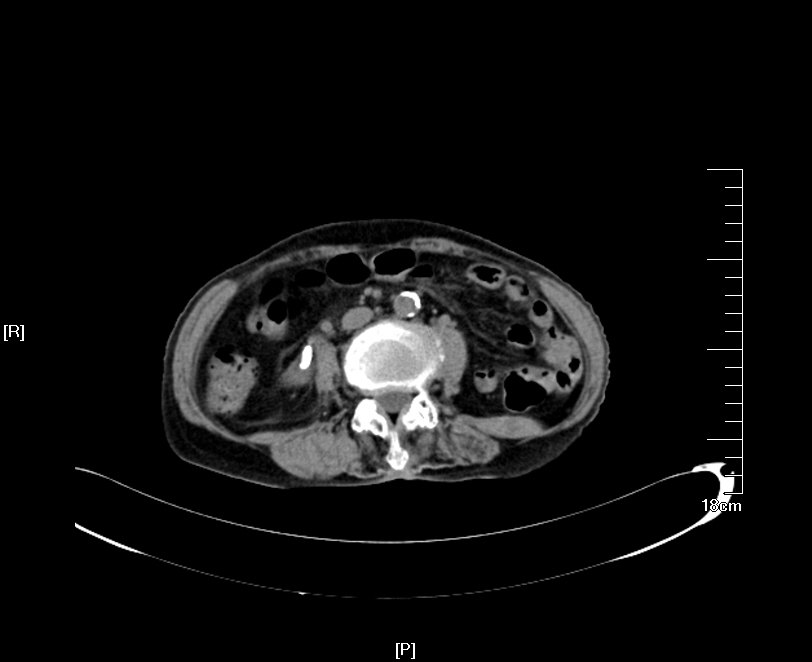

2016年04月手术患者,女性,32岁,昆山人,五年前曾因右输尿管结石引起肾绞痛于当地消炎补液解痉排石处理,疼痛缓解后未于重视,其间从未予复查,2周前出现右腰痛,与当地诊所就诊后予以震波碎石无效,并出现发热,急诊来我院就诊,CT:右肾萎缩,右侧肾脏积水,右侧输尿管多发结石形成石街约4.5*1.5cm,GFR:右侧17.2ml/min,左侧43.2ml/min。因左侧健肾代偿,肾功能正常:Cr 132umol/L;术前诊断:右输尿管下段多发结石 右肾萎缩 肾功能不全,鉴于右输尿管结石梗阻时间太长,肾功能不全,已处于失代偿期,最终也只能行右侧输尿管下段切开取术,解除输尿管下段梗阻,尽可能保护已经萎缩的肾脏,该患者预后不良。

增强CT检查提示:右侧肾脏积水,右肾萎缩,右输尿管下段多发结石

KUB提示右输尿管下段结石呈石街样排列,引起右输尿管完全梗阻,导致右肾萎缩